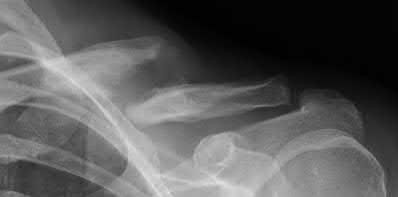

Question 12

A 55-year-old patient presents with a slowly enlarging, painful mass in the proximal humerus.

Biopsy reveals a hyaline cartilage matrix with cellular atypia, confirming a diagnosis of central conventional chondrosarcoma. Which of the following genetic mutations is most frequently identified in this specific tumor?

Explanation

Mutations in the isocitrate dehydrogenase genes, IDH1 and IDH2, are found in up to 50-60% of central conventional chondrosarcomas and enchondromas. EXT1 and EXT2 mutations are characteristic of multiple hereditary exostoses (osteochondromas). GNAS mutations are seen in fibrous dysplasia. TP53 and RB1 mutations are hallmark aberrations in osteosarcoma.